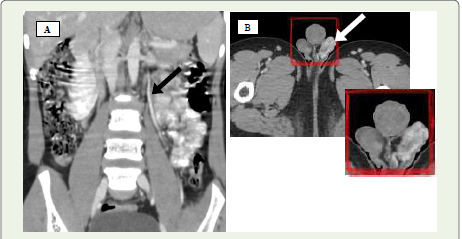

Figure 3 A-C: A 17-year-old male presenting with swelling in the left

scrotal region. (A) Axial contrast-enhanced CT image demonstrates the

characteristic “beak sign” (white solid arrow) due to narrowing of the left

renal vein. (B) Axial CT showing a reduced aortomesenteric distance (AMD)

measuring approximately 8 mm. (C) Sagittal contrast-enhanced CT reveals

a sharply decreased aortomesenteric angle (AMA) of around 48°.

Figure 4 A, B: (A) Coronal contrast-enhanced CT image displays a

prominently dilated left testicular vein (black arrow). (B) Axial contrast-enhanced

CT scan of the scrotum reveals a cluster of tortuous, enhancing

veins within the left scrotal sac (white solid arrow), consistent with a left-sided

varicocele.

Figure 5 Axial contrast-enhanced CT of a 33-year-old woman demonstrates

a retro-aortic course of the left renal vein (white arrow), an incidental finding

consistent with the posterior variant of Nutcracker Syndrome.

CT imaging findings:

On axial CT, the “beak sign” is seen as abrupt narrowing of the

LRV at the point where it passes between the SMA and aorta, forming

an acute angle [Figure 3A] [11,12]. Sagittal reconstructions help assess the aortomesenteric angle (AMA), which normally ranges from 38°–

56°; angles under 35° are suggestive of the syndrome [13,14]. Affected

individuals also demonstrate a reduced aortomesenteric distance

(AMD), typically narrowed from the normal 10–28 mm to 2–8 mm

[1,15] [Figure 3B], [Figure 3C]. A pre- to post-compression LRV diameter ratio exceeding 2.25 has been shown to yield 91% sensitivity

and specificity for diagnosis [16]. CT may also reveal dilated gonadal

veins and pelvic varicosities, although it cannot assess blood flow

velocity or direction [11] [Figure 4A], [Figure 4B].Management: